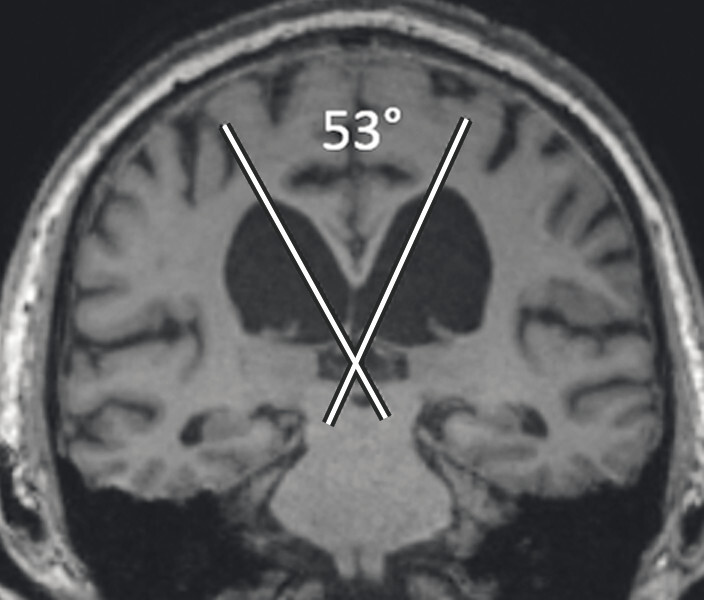

Typische Aspekte im MRT. Das DESH-Zeichen (a, Pfeile) ist am zuverlässigsten in Bezug auf das Erkennen des typischen Erscheinungsbilds eines Normaldruckhydrozephalus (a, b). Um ein weiteres typisches Zeichen, den spitzen Corpus-callosum-Winkel, verlässlich bestimmen zu können, ist es wichtig, den T1w 3-D-Datensatz exakt in der Commissura-anterior-Commissura-posterior-Linie zu orientieren (d, Pfeile) und den Winkel der Corpus-callosum-Schenkel in der koronaren Ebene auf Niveau der Commissura posterior (d, blaue Linie) zu bestimmen. Ein Corpus-callosum-Winkel von weniger als 90° gilt als anomal und als Hinweis auf den Aspekt eines Normaldruckhydrozephalus (e).

d Spitzer Corpus-callosum-Winkel: Orientierung des T1w 3-D-Datensatzes exakt in der Commissura-anterior-Commissura-posterior-Linie (blaue Linie) und Bestimmung des Winkels der Corpus-callosum-Schenkel in der koronaren Ebene auf Niveau der Commissura posterior.

e Spitzer Corpus-callosum-Winkel: Beispiel eines pathologischen Corpus-callosum-Winkels.